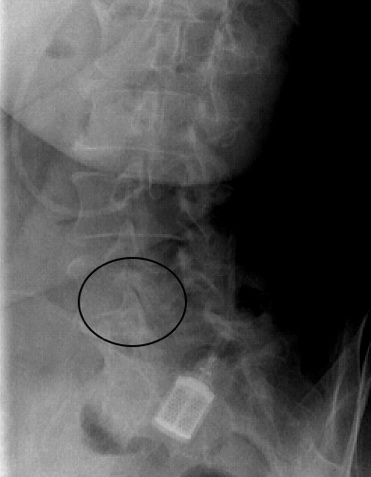

X-rays revealed bilateral FEMORO ACETABULAR IMPINGEMENT SYNDROME Pincer deformity but fortunately minimal degenerative hip arthritis ... highly treatable with chiropractic.

The large Pincer deformities of FAIS are readily seen in both hips with no obvious CAM deformities.

There was a marked right sacroiliac fixation and all lumbars were extremely tender. A hyperlordosis was evident. Prominence of the L5 spinous process suggested the possibility of a spondylolysthesis, confirmed on X-ray, at two levels.

Fortunately there was no marked leg length inequality or scoliosis to complicate matters further. Nevertheless the severe degenerative facet changes are readily visible on the AP lumbar X-ray.